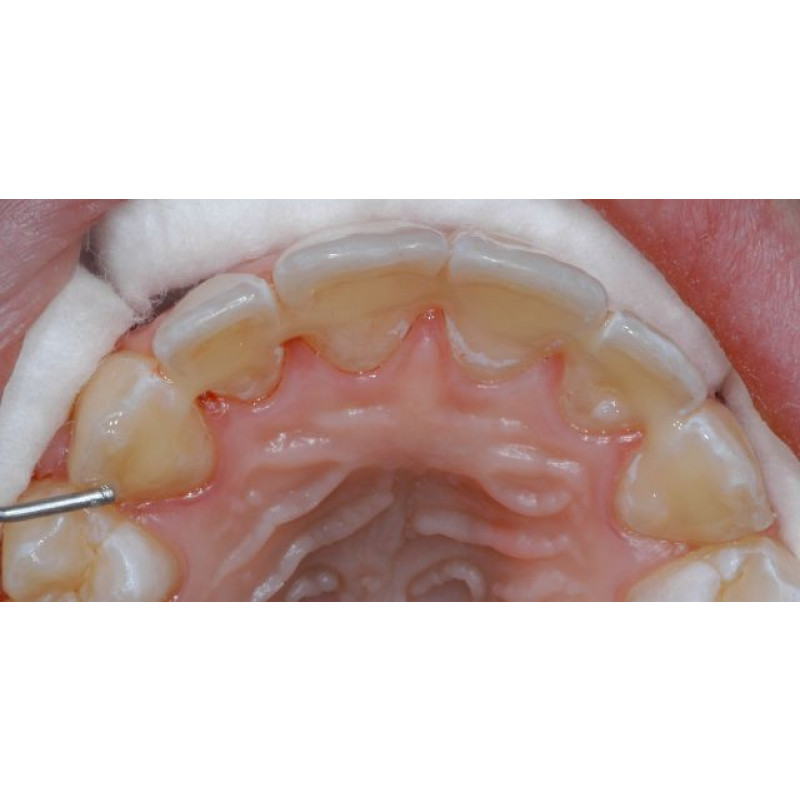

L'utilisation du GC everStickORTHO est indiquée pendant la phase de contention esthétique après un traitement orthodontique actif. La matrice réunit les fibres de verre individuelles en un faisceau qui permet une manipulation et une adaptation faciles à la surface des dents.